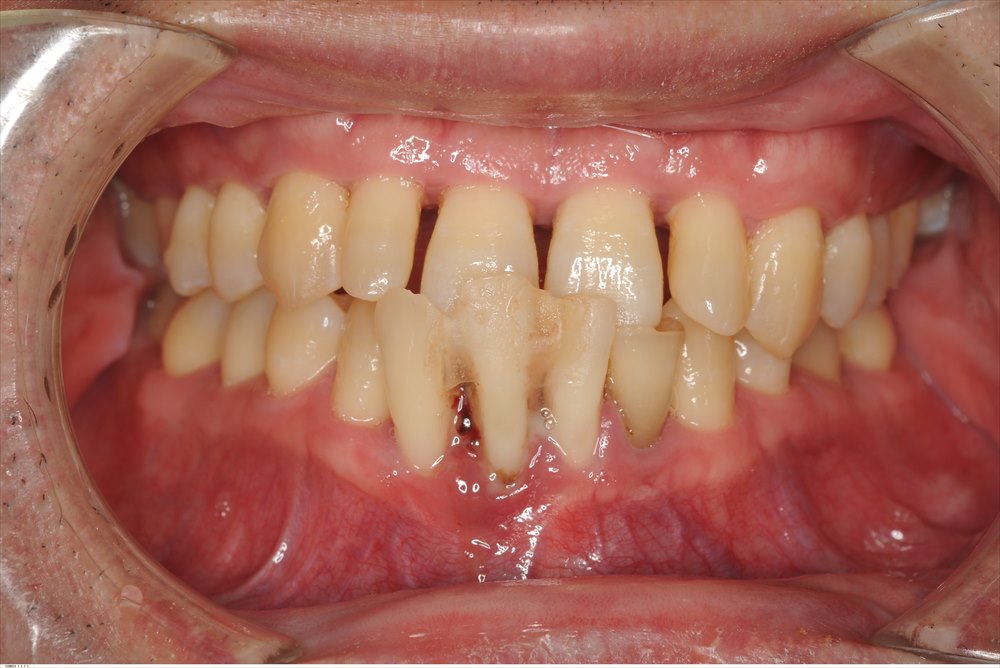

約1年半前に初診でいらした患者さま。重症の歯周病で来院されました。セカンドオピニオンです。

広範性・重度・侵襲性歯周炎と診断しました。

骨の量も全額的に少なく、下の前歯は抜けていました。

右下の6番 膿が出ていました。。。

ここは垂直的に骨が無くなっていました。ポケットは7mm。